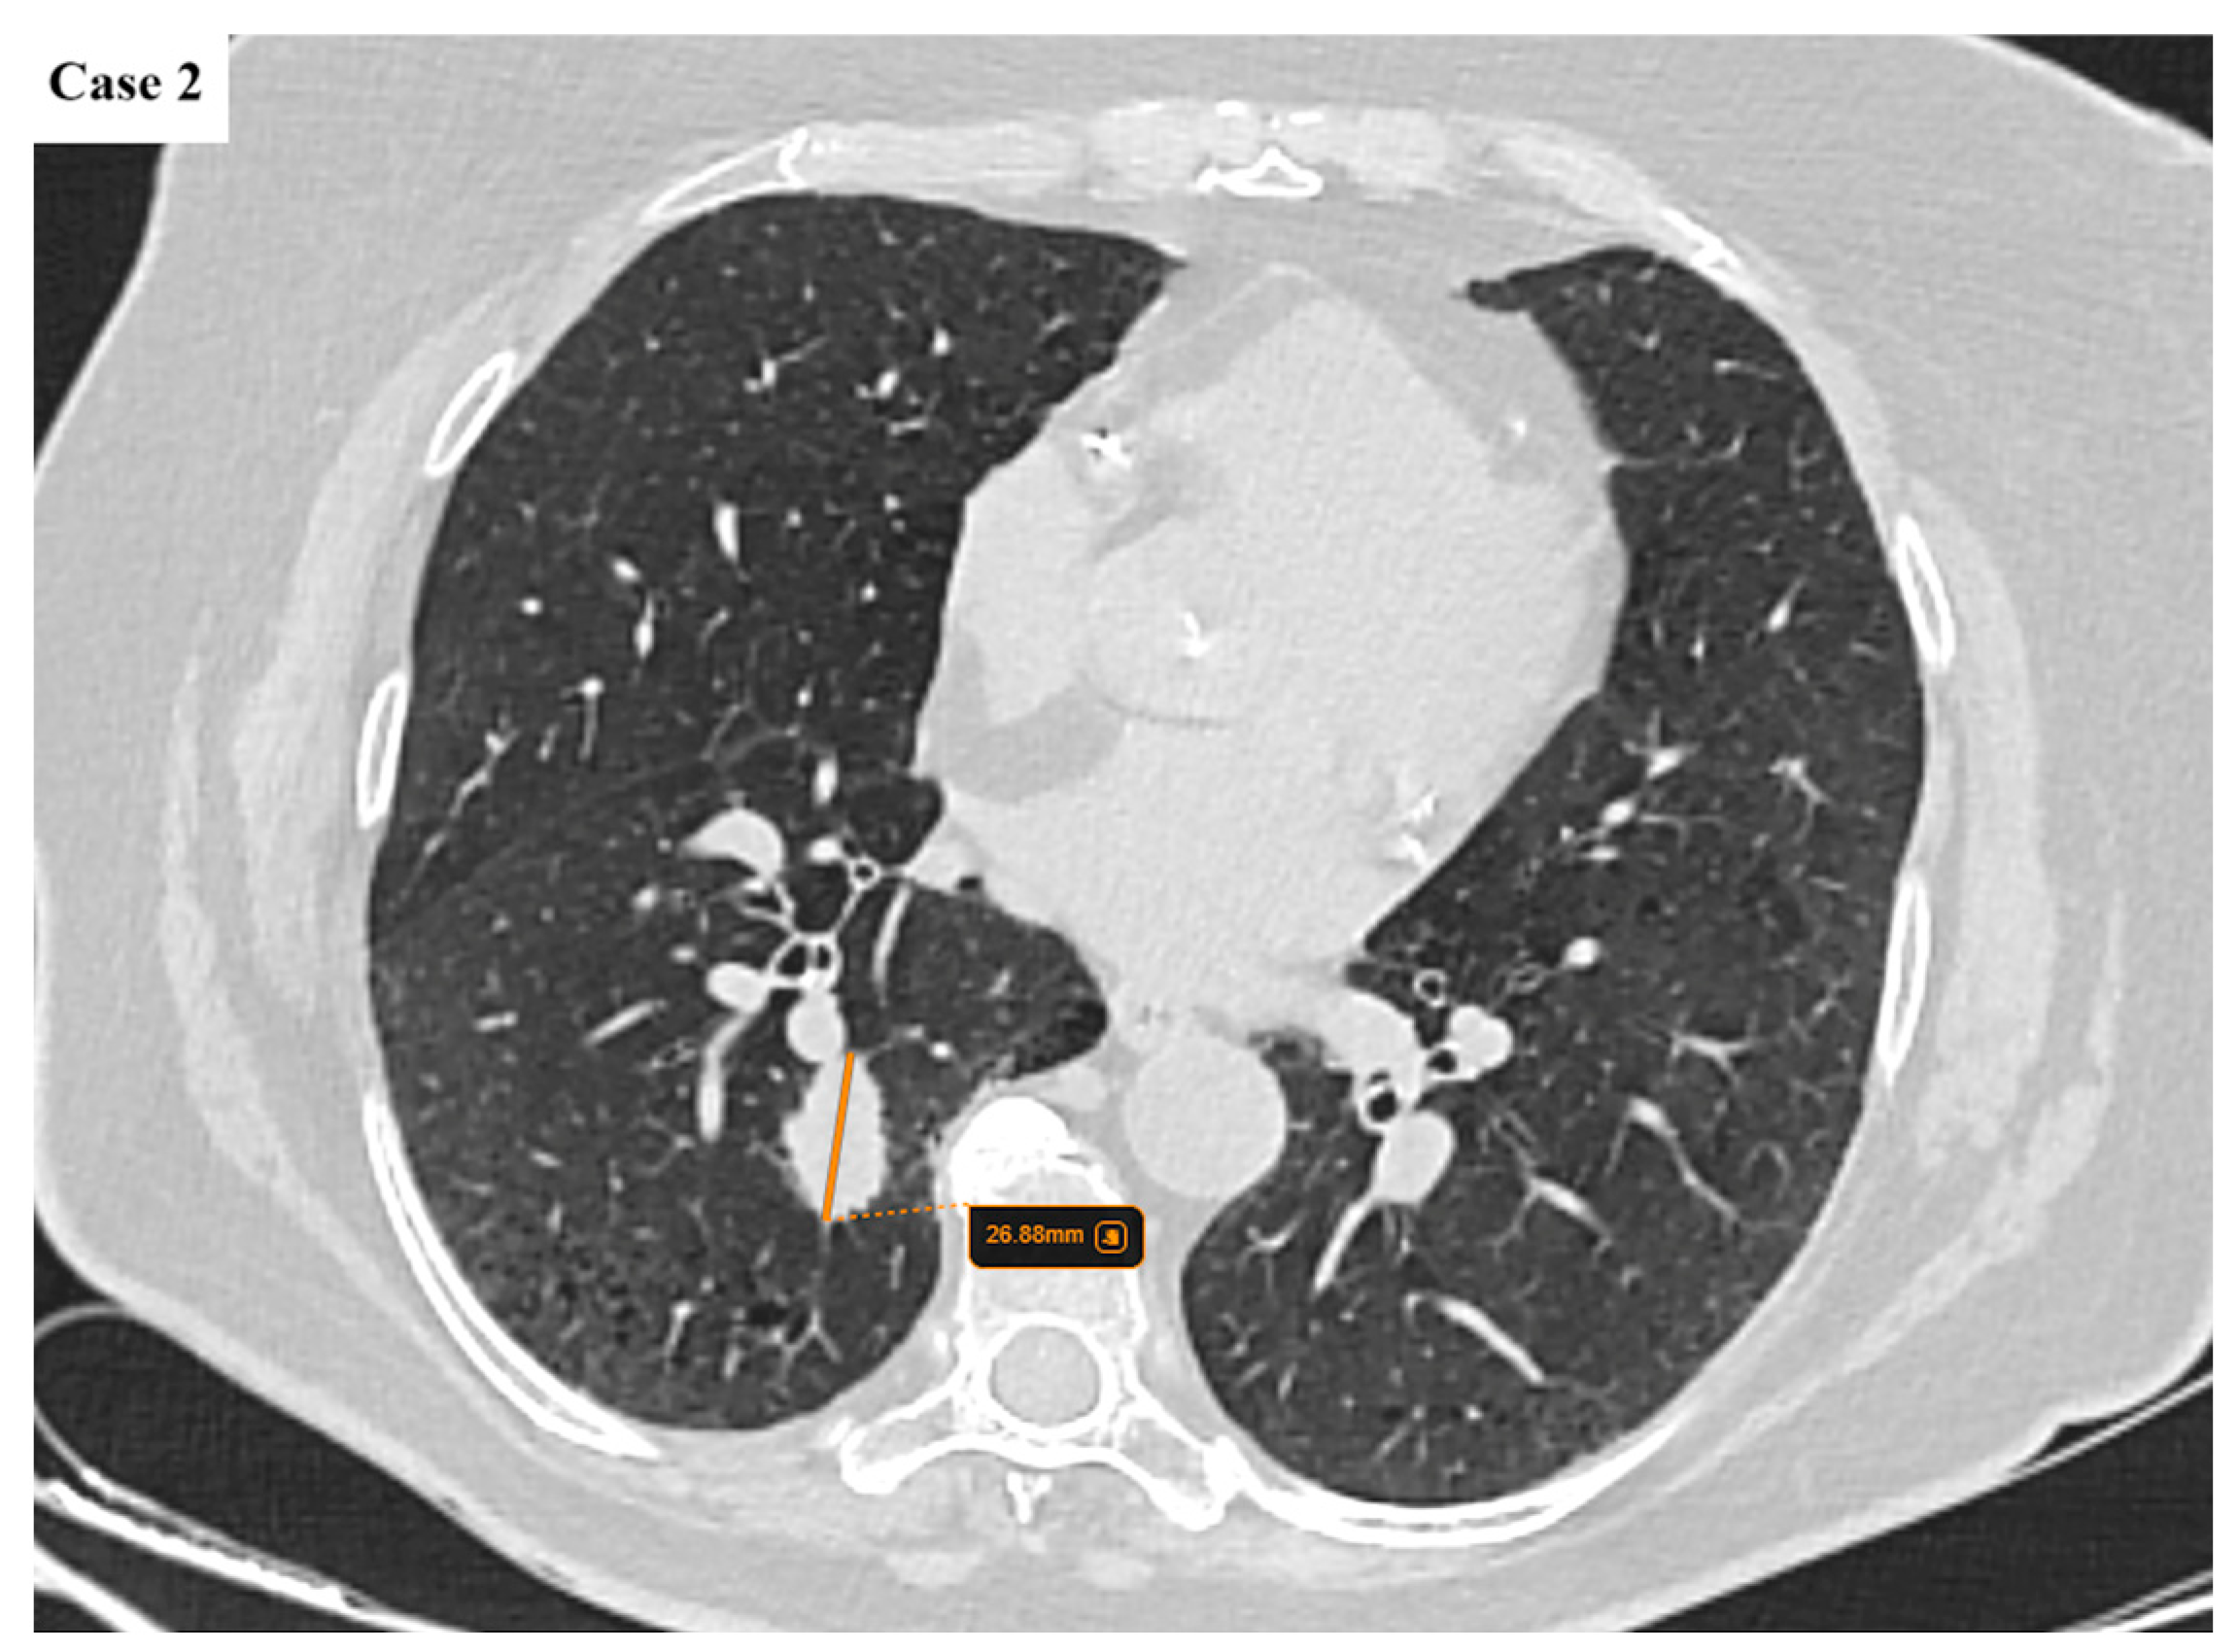

2.2. Data Collection and Imaging Evaluation

2.3. Staging Procedures

- N descriptor: subdivision of N2 disease into single-station (N2a) and multi-station (N2b);